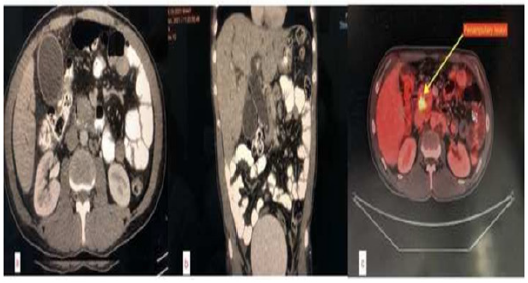

We report a 44-year-old man who presented with complains of jaundice, clay-coloured stools and generalised itching of 15 days duration along with anorexia and weakness. He was evaluated outside with CECT which showed periampullary lesion (Figure 1) and was initially managed with ERCP and plastic CBD stent placement for bilirubin of 23 mg/dl and ampullary biopsy which proved moderately differentiated adenocarcinoma on review at this centre. After relief of jaundice, he was planned for Whipple’s procedure.

On admission for surgery, he was asymptomatic and had no features of cholangitis and his ECOG performance score was 1. An 18-FDG PET/CT scan showed avid lesion in head of pancreas with dilated CBD and IHBRD with stent in-situ (Figure 1). His labs noted with total and direct bilirubin of 3.8 and 2.5 mg/dl respectively, amylase 308 U/L, lipase 3016 U/L. Other hematological and biochemical parameters were within normal limits. His preoperative serum albumin was 2.9 g/dl with AG ratio of 0.6 and was started on high protein diet for optimization for surgery. Through a midline laparotomy approach, the lesion was deemed resectable in standard fashion as described by Evans [2]. Multiple lymph nodes were found in stations 8, 12, periportal and retro duodenal stations with largest node reaching up to 3 cm in size as detected intraoperatively. Complete resection with adequate lymph node dissection was performed by classical Whipple’s procedure (Figure 2). Reconstruction was achieved with duct-to-mucosa pancreatico-gastrostomy (PG), end to side hepaticojejunostomy and end to side gastrojejunostomy. Closure was done over two drains in abdomen - one in lesser sac near pancreatic anastomosis on left side and another in Morrison’s pouch taken out from right side of the abdomen. A feeding jejunostomy (FJ) was created for early postoperative nutritional support. Total operative time was 07 hours and estimated blood loss was 400ml.